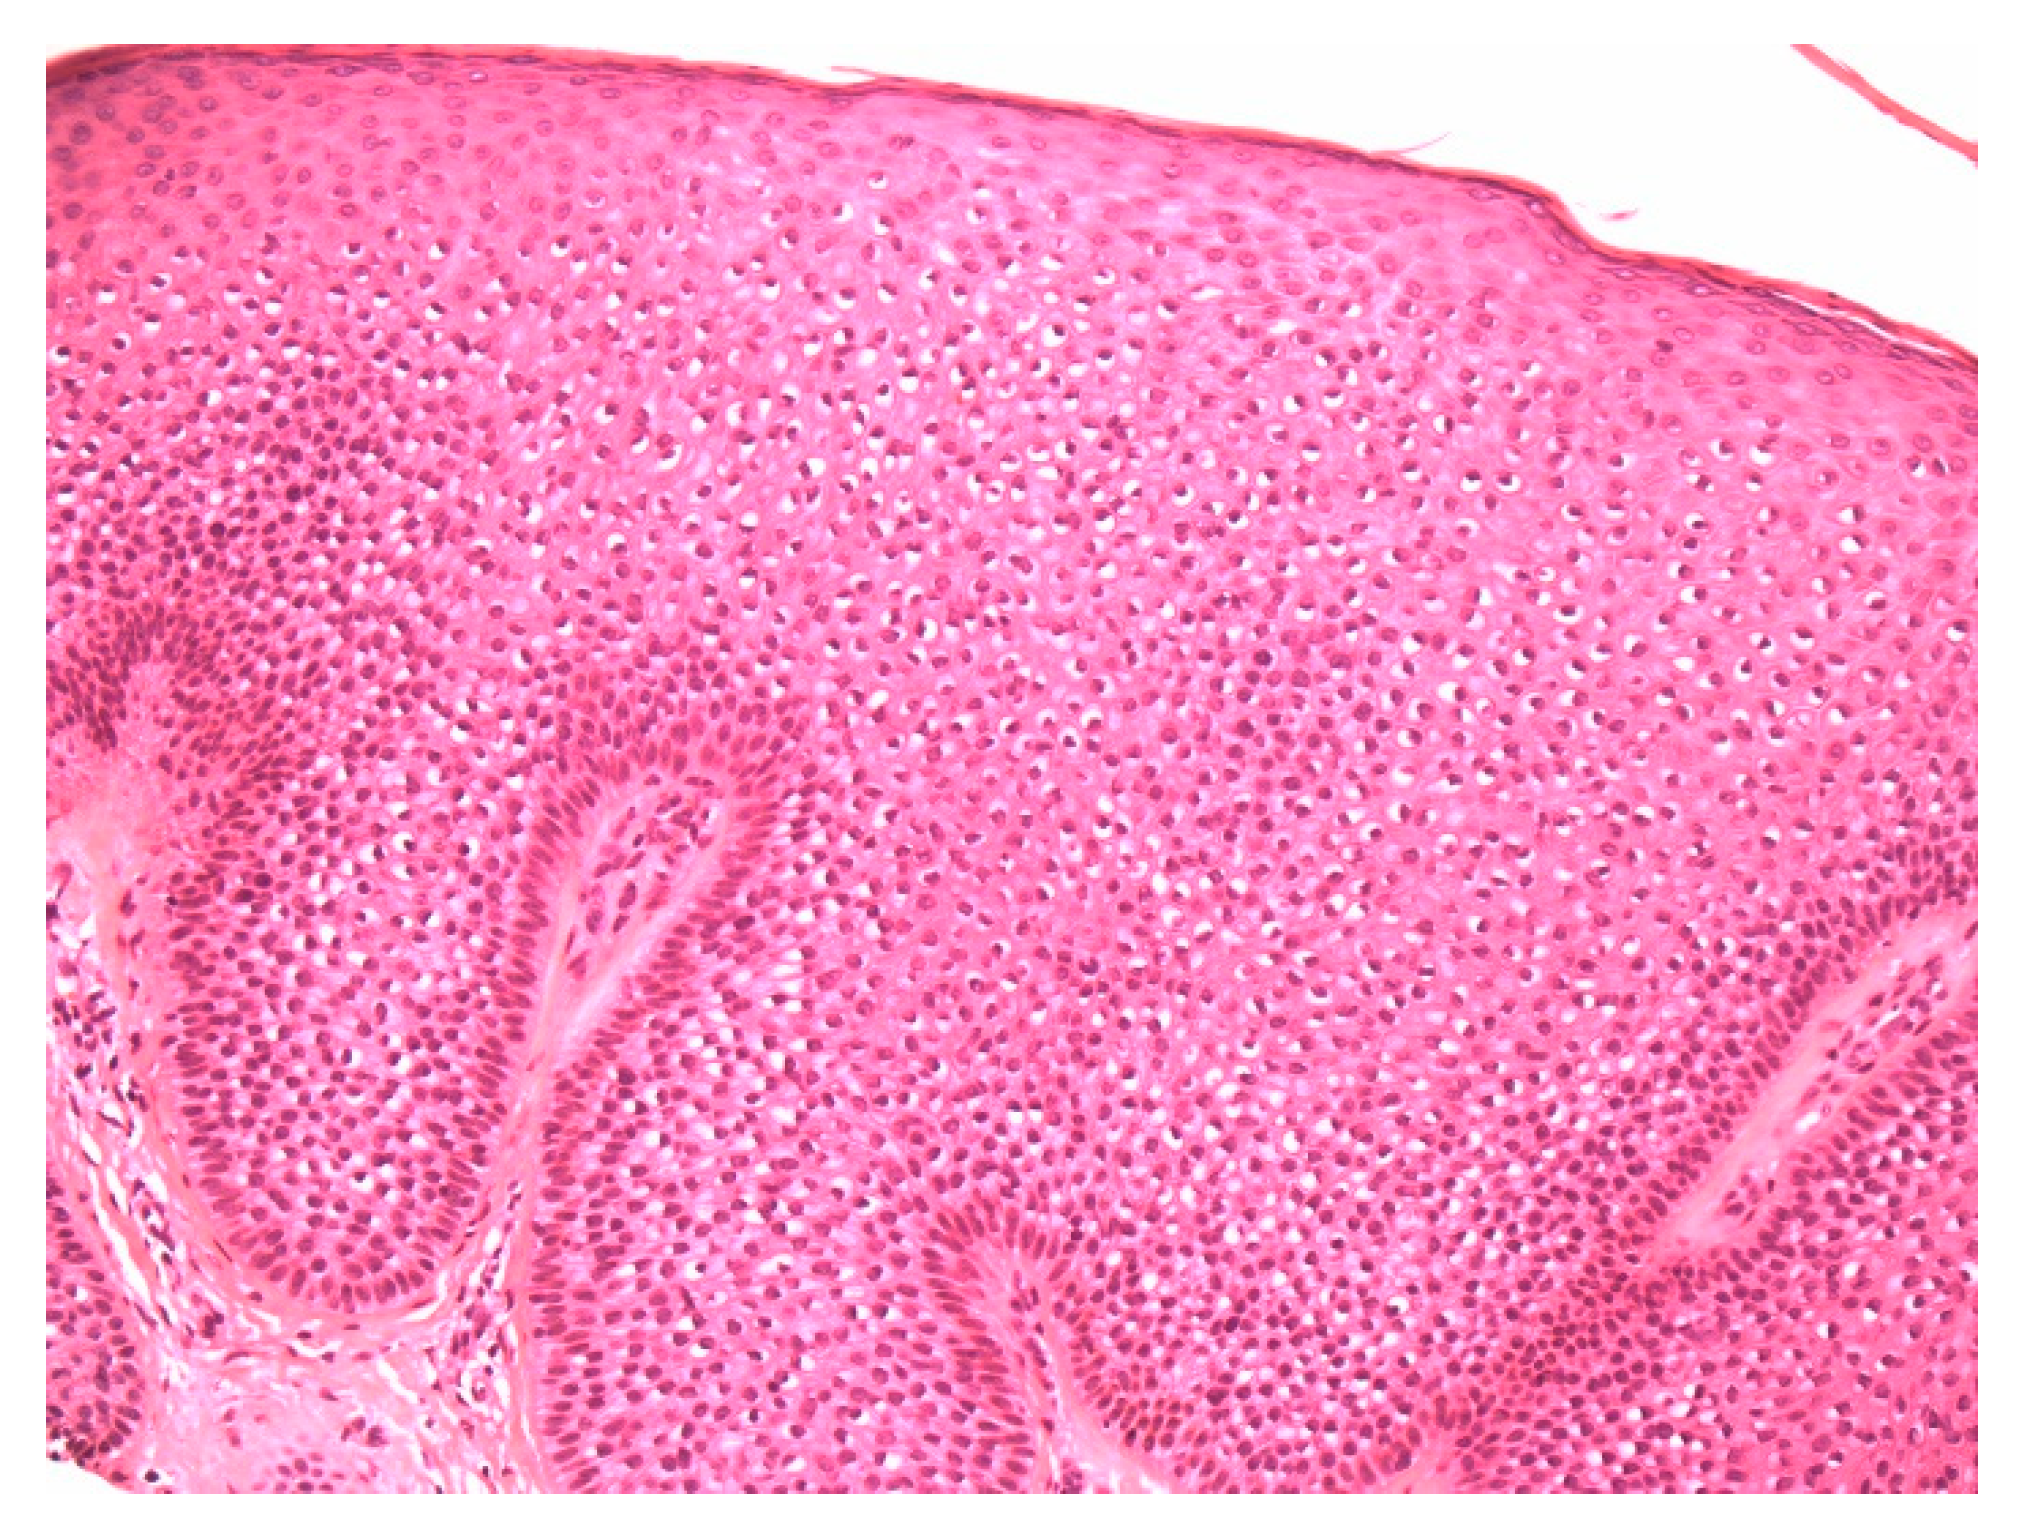

Figure 2.

High-power view demonstrating distinct large perinuclear vacuoles and peripheral palisading of basal keratinocytes.